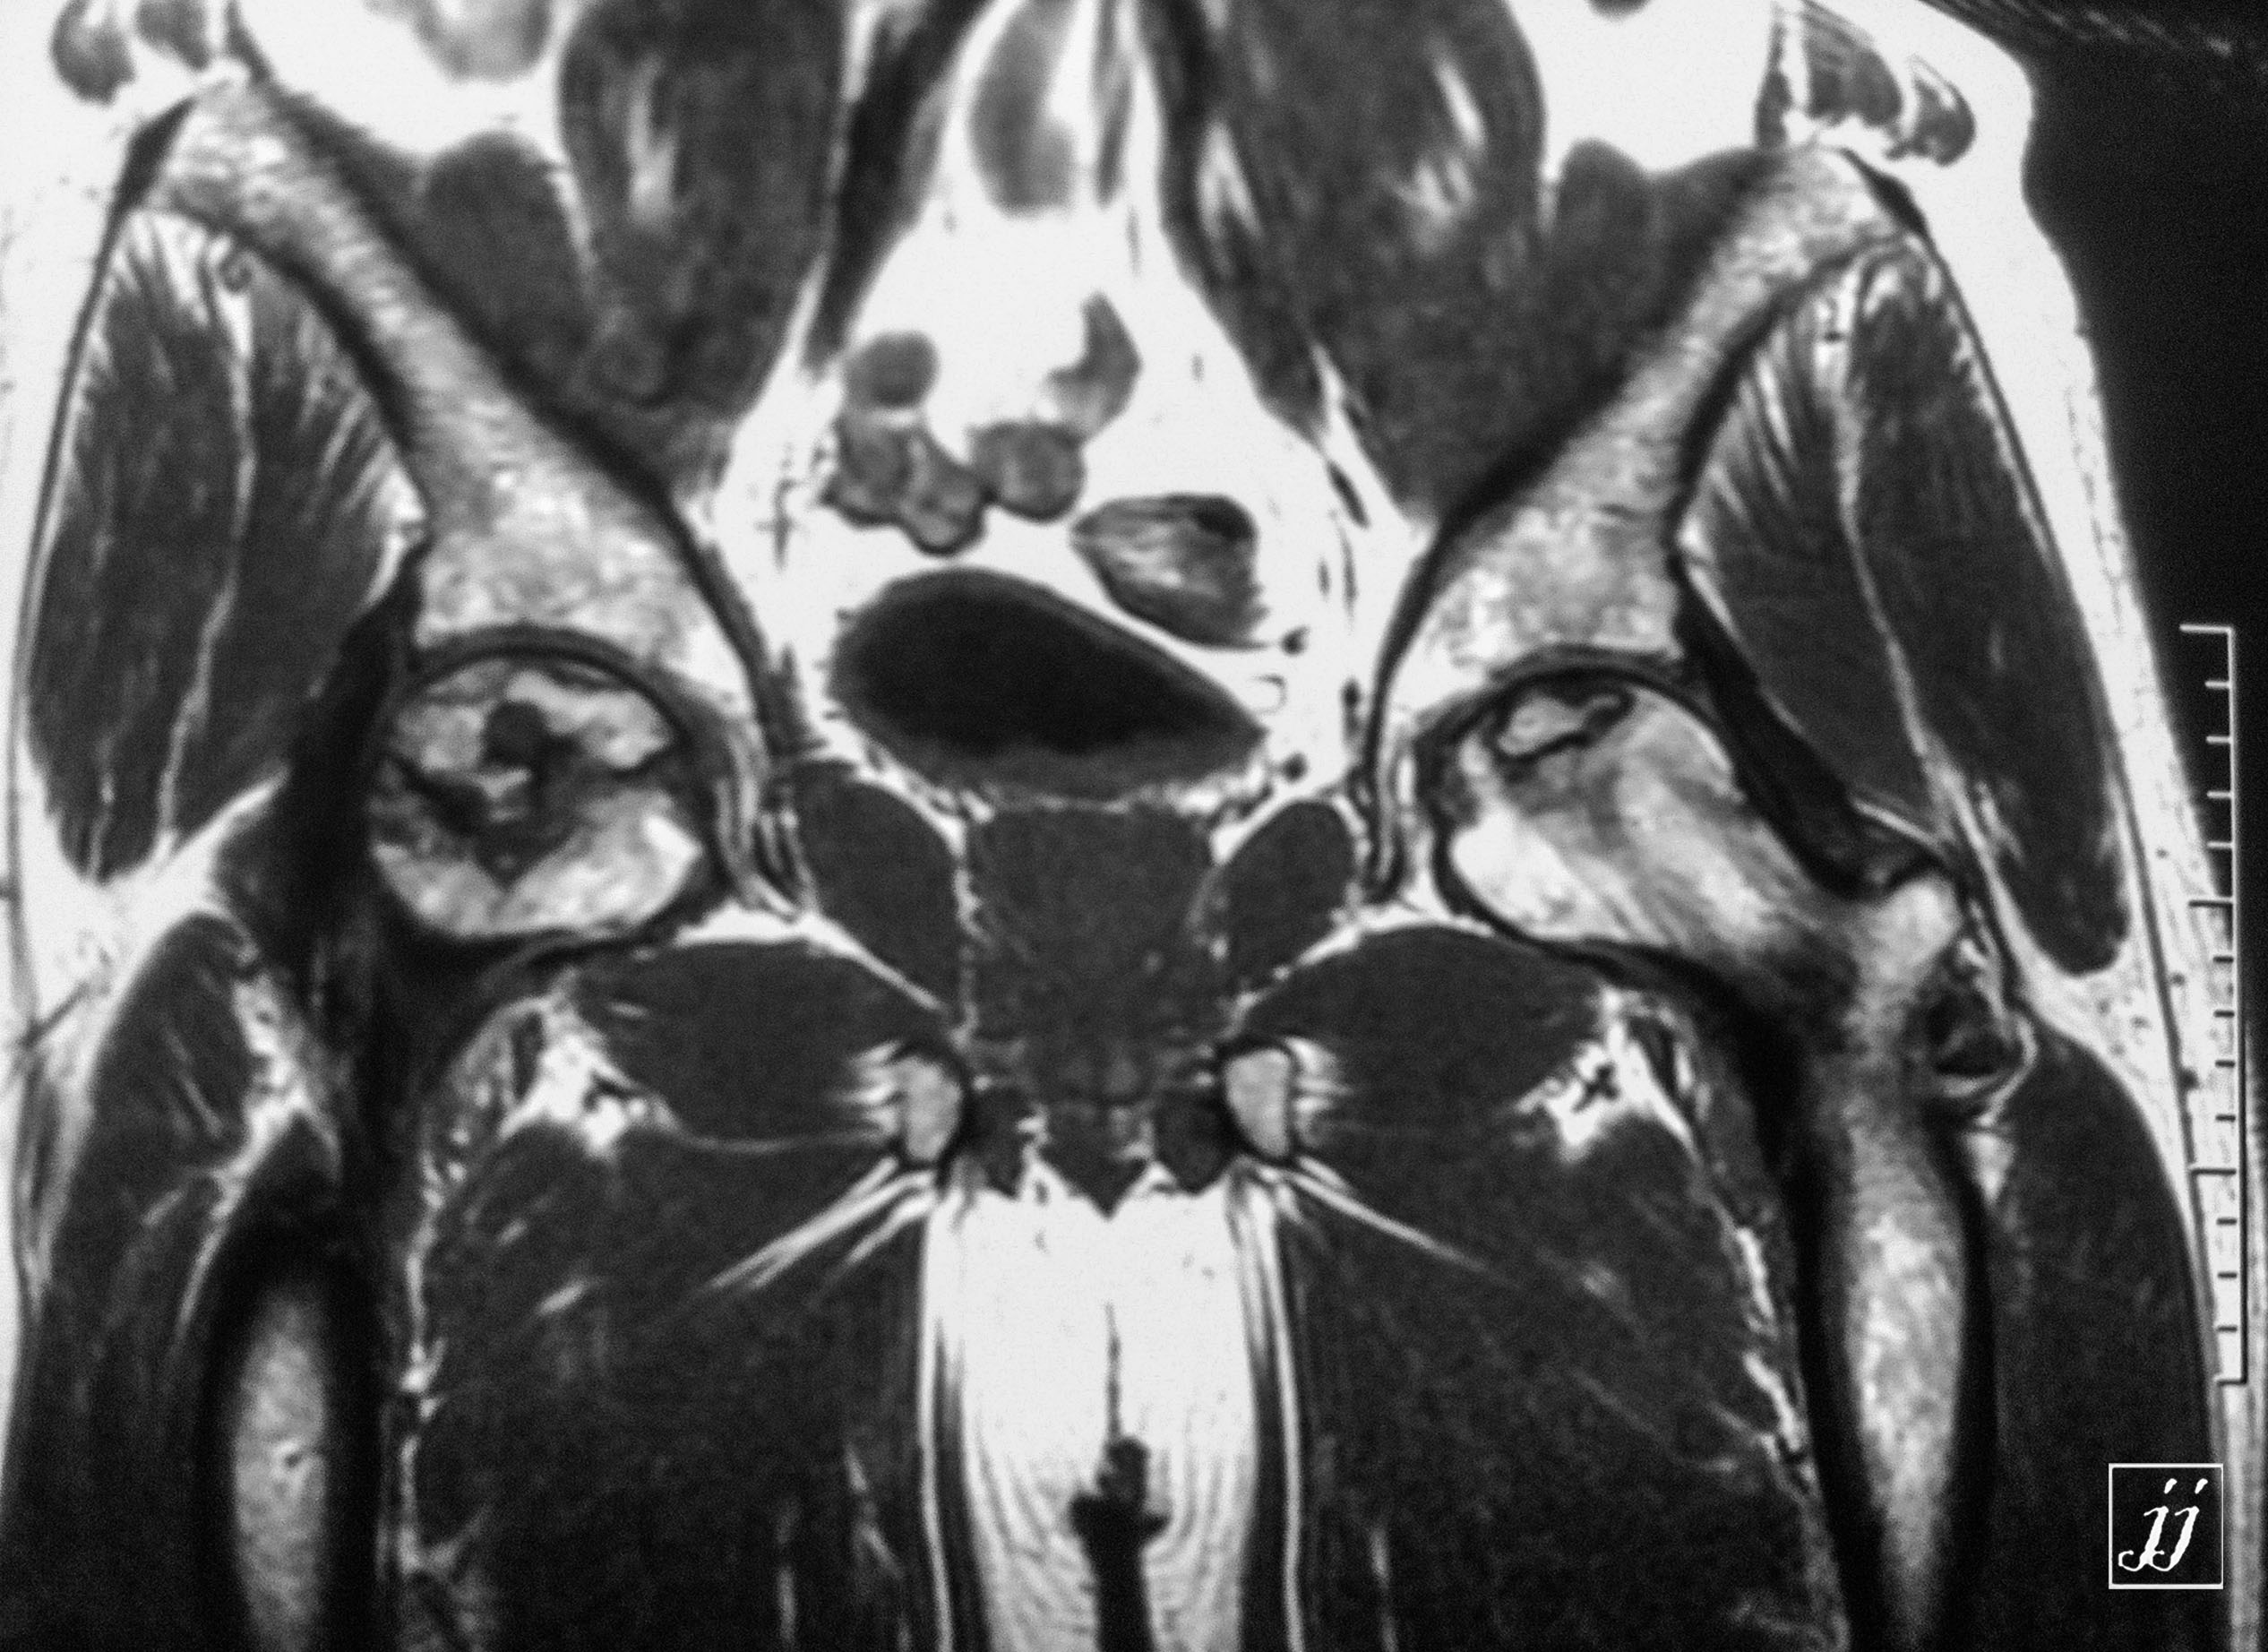

Abdomen- left gluteal iliac inflammatory disease and splenomegaly and no left kidney (21)